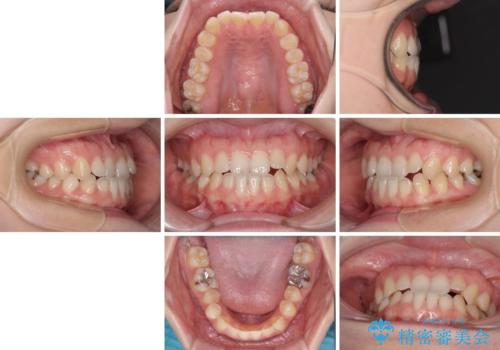

前歯のクロスバイト インビザラインによる矯正治療

- 前歯のクロスバイトとデコボコを気にして来院された患者様です。

骨格的に下顎前突傾向であるため、自己管理が煩わしくないようであれば、インビザラインによる矯正治療がお勧めとなります。

インビザラインを用い、下顎歯列を後方に移動させながら全市の被蓋を改善し、歯並びを整えていくこととしました。